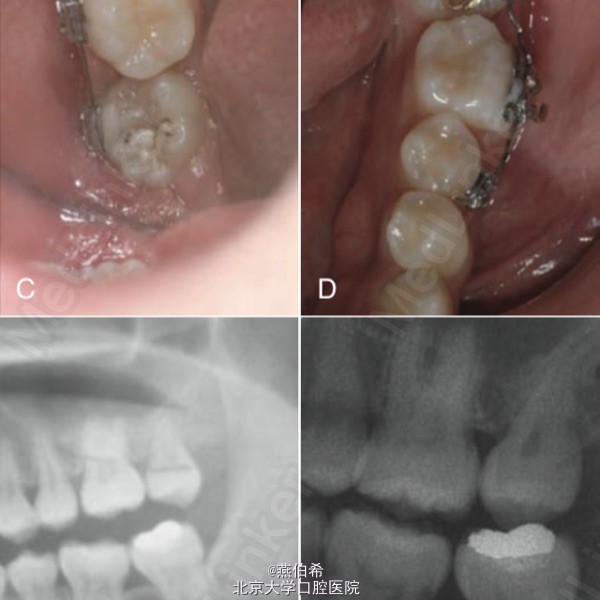

局部正畸,磨牙后垫种植钉直立阻生7

Orthodontics: Current Principals and Techniques (5ed)上病例。美籍韩裔医生完成。下7,8阻生,拔8同时打钉子,直立7